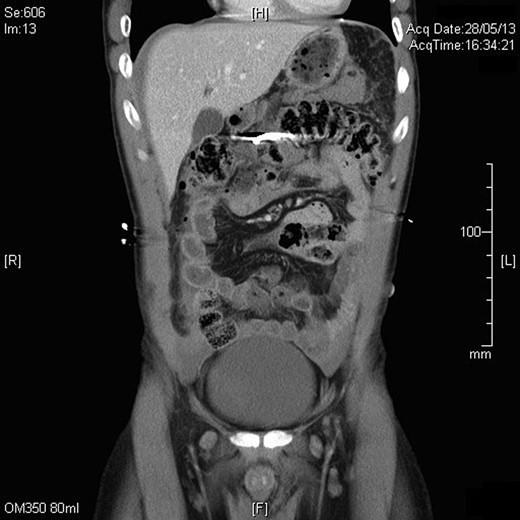

The patient arrived in the emergency department of The Alfred Hospital 25 min after the accident. A FAST scan (Focused Assessment with Sonography for Trauma) was positive. A plain abdominal radiograph confirmed the presence of a single nail in the abdomen. A subsequent CT scan showed that the nail was positioned within the transverse colon with free air and fluid surrounding the liver, spleen and paracolic gutters, and a perforation of the horizontal duodenum with retroperitoneal free air and fluid. No vascular injury was seen (Figs 1 and 2).

Slice from the CT abdomen showing the position of the nail in the abdomen.